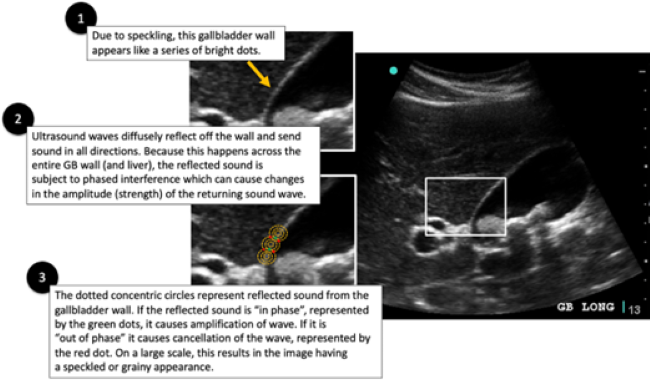

Compounding this phenomenon is another physical property of waves, known as phasicity. When two waves of the same frequency line up, such that their peaks and troughs are the exact same, they are said to be “in-phase.” Two in-phase waves undergo constructive interference where the amplitude of each wave is summed together to create a new wave with increased amplitude. When this wave with increased amplitude is received by the ultrasound machine, it is given a brighter shade of grey and is seen as brighter on the screen.  In contrast, two waves that have their peaks and troughs in exact opposite positions, are known as “out-of-phase.” This results in deconstructive interference where both waves cancel each other out. In this case, no sound signal is received by the machine and appears as anechoic on the screen.

The overall effect of diffuse reflectors causing constructive and deconstructive interference across the entire tissue, gives the ultrasound image a speckled or grainy appearance. See Figure 1. In reality, the tissue is not grainy or speckled at all. Rather the ultrasound machine interprets the tissue as having a grainy texture because of how sound interacts with diffuse reflectors and due to in-phase and out-of-phase waves. This speckling is known as “speckle artifact.” Overall, this is not desirable in an ultrasound image. In particular, this speckle artifact leads to poor demarcation of tissue interfaces and fails to show subtle differences that should be present in adjacent tissues. To reduce speckling, ultrasound manufacturers use a variety of post processing algorithms. These algorithms are proprietary and differ from one manufacturer to the next. Often, a particular post-processing function or feature responsible for reducing speckle is given a name by the manufacturer. Table 1 lists the four vendors we met with and the name of the feature that reduces speckle.

Lipliner_Fig1.pngFigure 1. Constructive and Deconstructive Interference of Diffuse Reflectors on Ultrasound Images